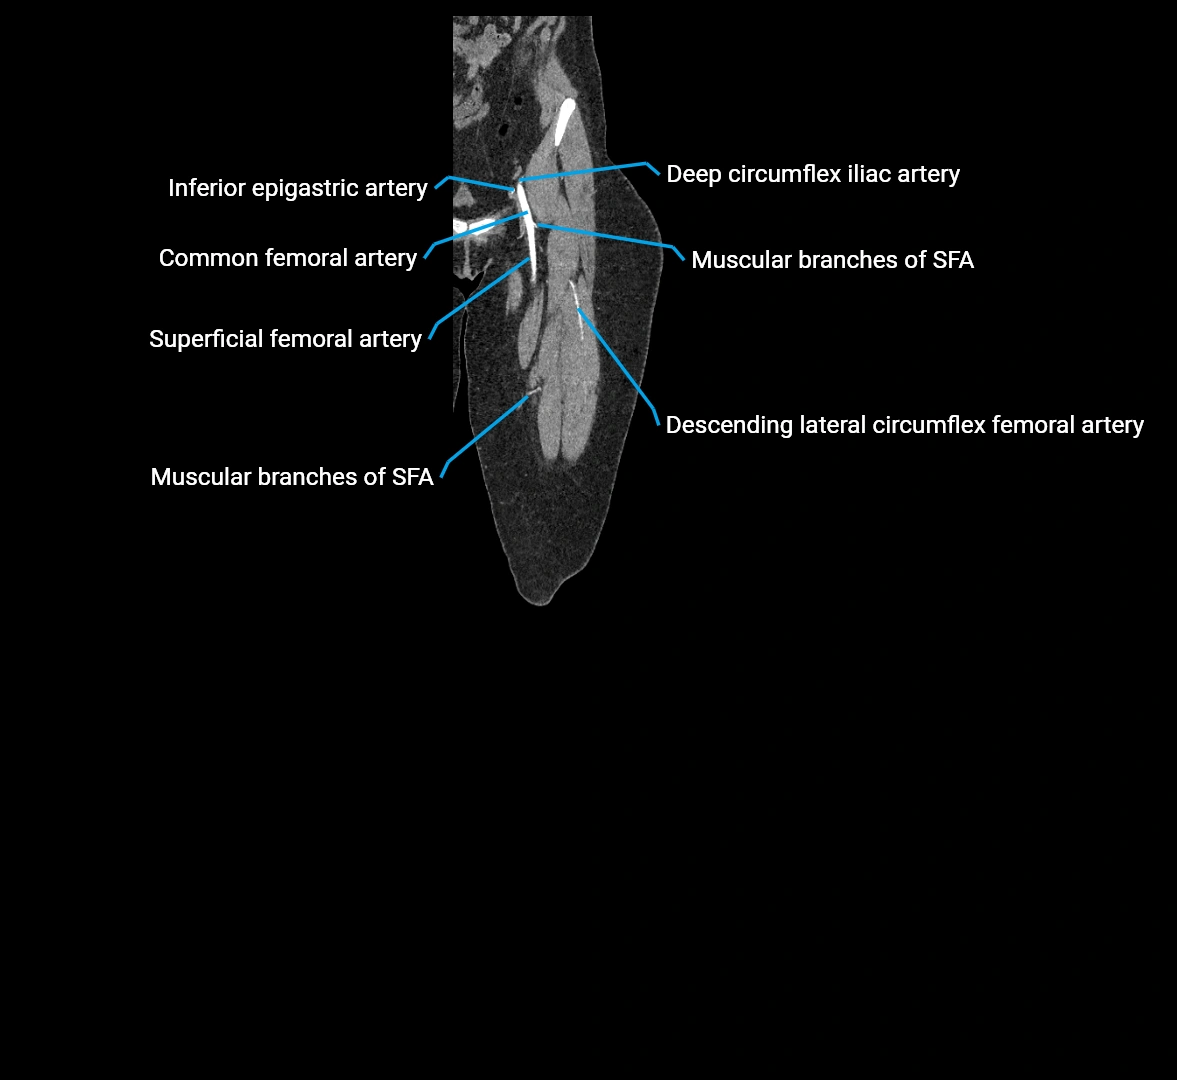

CT images

image

Contrast-enhanced CT (CTA):

• Gold standard for abdominal aortic imaging

• Provides excellent detail of lumen, wall, aneurysm, thrombus, and branch vessels

• Multiplanar and 3D reconstructions help in aneurysm measurement, stent graft planning, and dissection evaluation